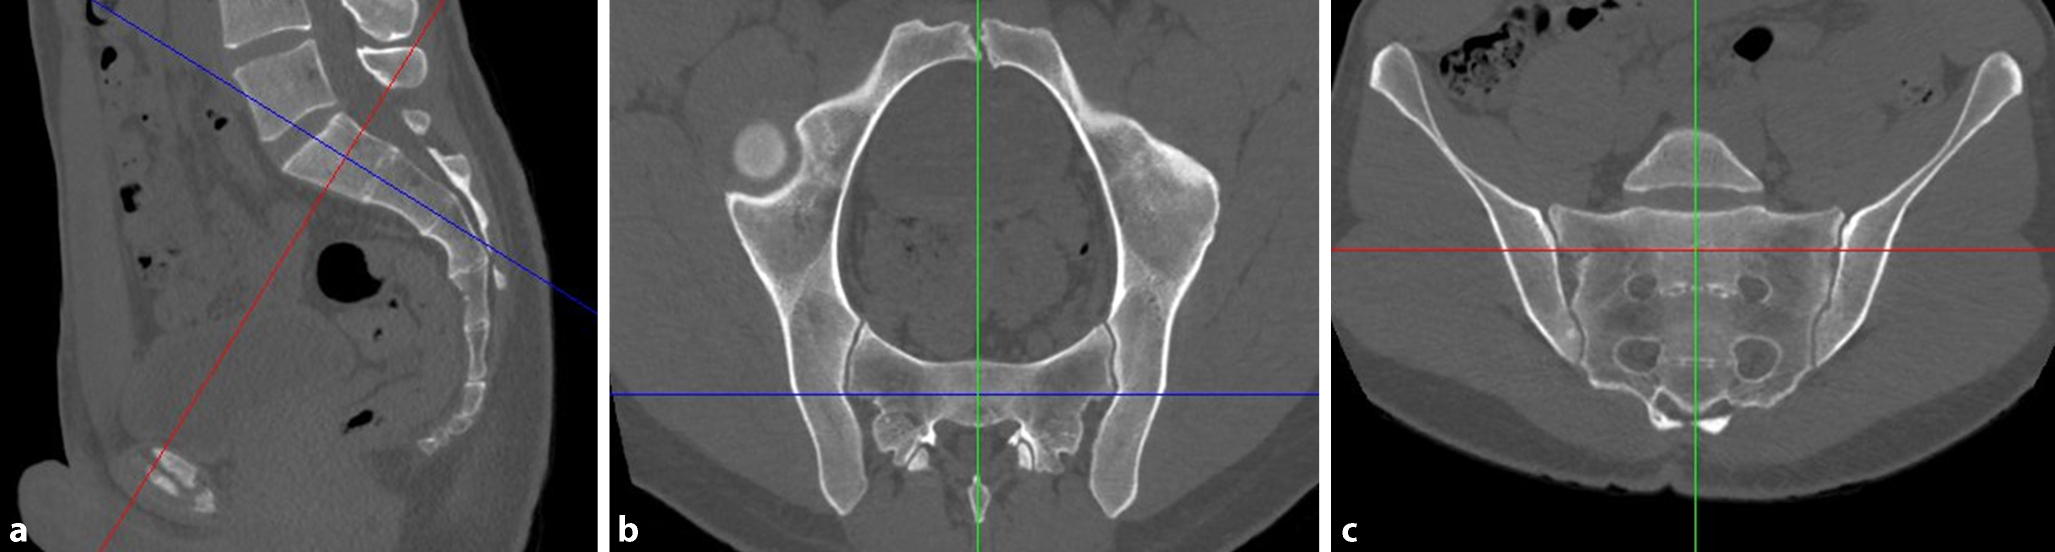

Third step—assessing transverse screw trajectories

Intraoperatively, the S1 starting point is identified in the lateral view (Fig. 3a). For preoperative planning using multiplanar CT reconstructions, the lateral view at the level of the S1 body is segmented in a 3 × 3 grid with 9 zones. An upper, middle and lower third are distinguished from cranial to caudal, which corresponds to the outlet view. An anterior, central and posterior third are distinguished from anterior to posterior, which corresponds to the inlet view. Accordingly, the zones are labeled as acronyms of two uppercase letters. For example, the “UA” zone corresponds to the upper and anterior third, the “MC” zone to the middle and central third and the “LP” zone to the lower and posterior third.

Fig. 3

Third step of preoperative work-up: assessing transverse screw trajectories. a The lateral view at the level of the S1 body is segmented in a 3 × 3 grid with 9 zones, b transverse screw trajectory. U upper, M middle, L lower, A anterior, C central, P posterior, red circumscribed letters transverse screw trajectories with safe osseous corridors, Blue line coronal axis, green line sagittal axis

Bild vergrößern

A transverse screw trajectory (Fig. 3b) following one of the nine zones is preferable over an oblique screw trajectory, which crosses zone borders, for the following two reasons. First, a transverse trajectory allows for the safe use of longer screws or even for the use of transiliac–transsacral screws or bars. Second, the intraoperative two-dimensional fluoroscopic control is much more demanding for oblique trajectories.

Within the transverse screw trajectories, central transverse trajectories (UC, MC and LC) are preferable over anterior and posterior transverse trajectories for the following reason. Small intraoperative deviations from preoperative planning may result in posterior screw misplacement for posterior transverse trajectories (UP, MP and LP) with consecutive iatrogenic lesions of sacral nerve roots in the sacral canal. Small intraoperative deviations from preoperative planning may result in anterior screw misplacement for anterior transverse trajectories (UA, MA and LA) with consecutive iatrogenic lesions of lumbar nerve roots. In contrast, central transverse trajectories may compensate for small intraoperative deviations.

The assessment of the MC transverse trajectory is the first choice due to its central location. This trajectory is therefore also called “Bullseye trajectory”. In the present case there is an adequate osseous corridor for an MC trajectory. There is also an UC trajectory, while the LC trajectory is in close vicinity to the S1 nerve roots. The transverse screw trajectories with safe osseous corridors (MC and UC) are marked in the grid as depicted. Even in the presence of safe transverse trajectories it is advisable to preoperatively also assess safe oblique trajectories as shown below in order to be able to intraoperatively judge whether small intraoperative deviations from the preoperative plan are acceptable.